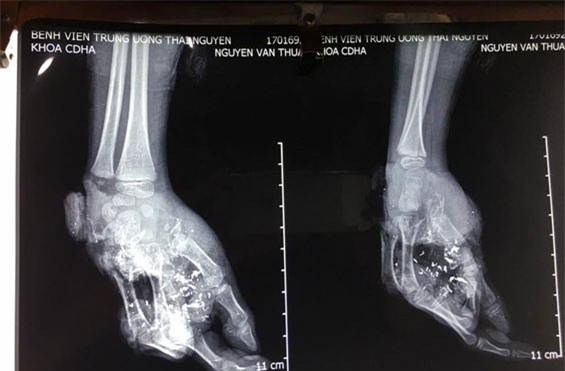

Trao đổi với chúng tôi, bác sĩ Nguyễn Thanh Tùng cho biết, quả pin phát nổ đã gây tổn thương nghiêm trọng. Bàn tay phải của Thuận mất toàn bộ xương bàn ngón giữa, áp út và ngón út; mất toàn bộ bờ ngoài bàn tay; tổn thương toàn bộ hệ thống gân bàn tay, xương bàn tay và gân cơ. Ngoài ra, khu vực lòng bàn tay có nhiều dị vật mảnh vỡ bằng kim loại.